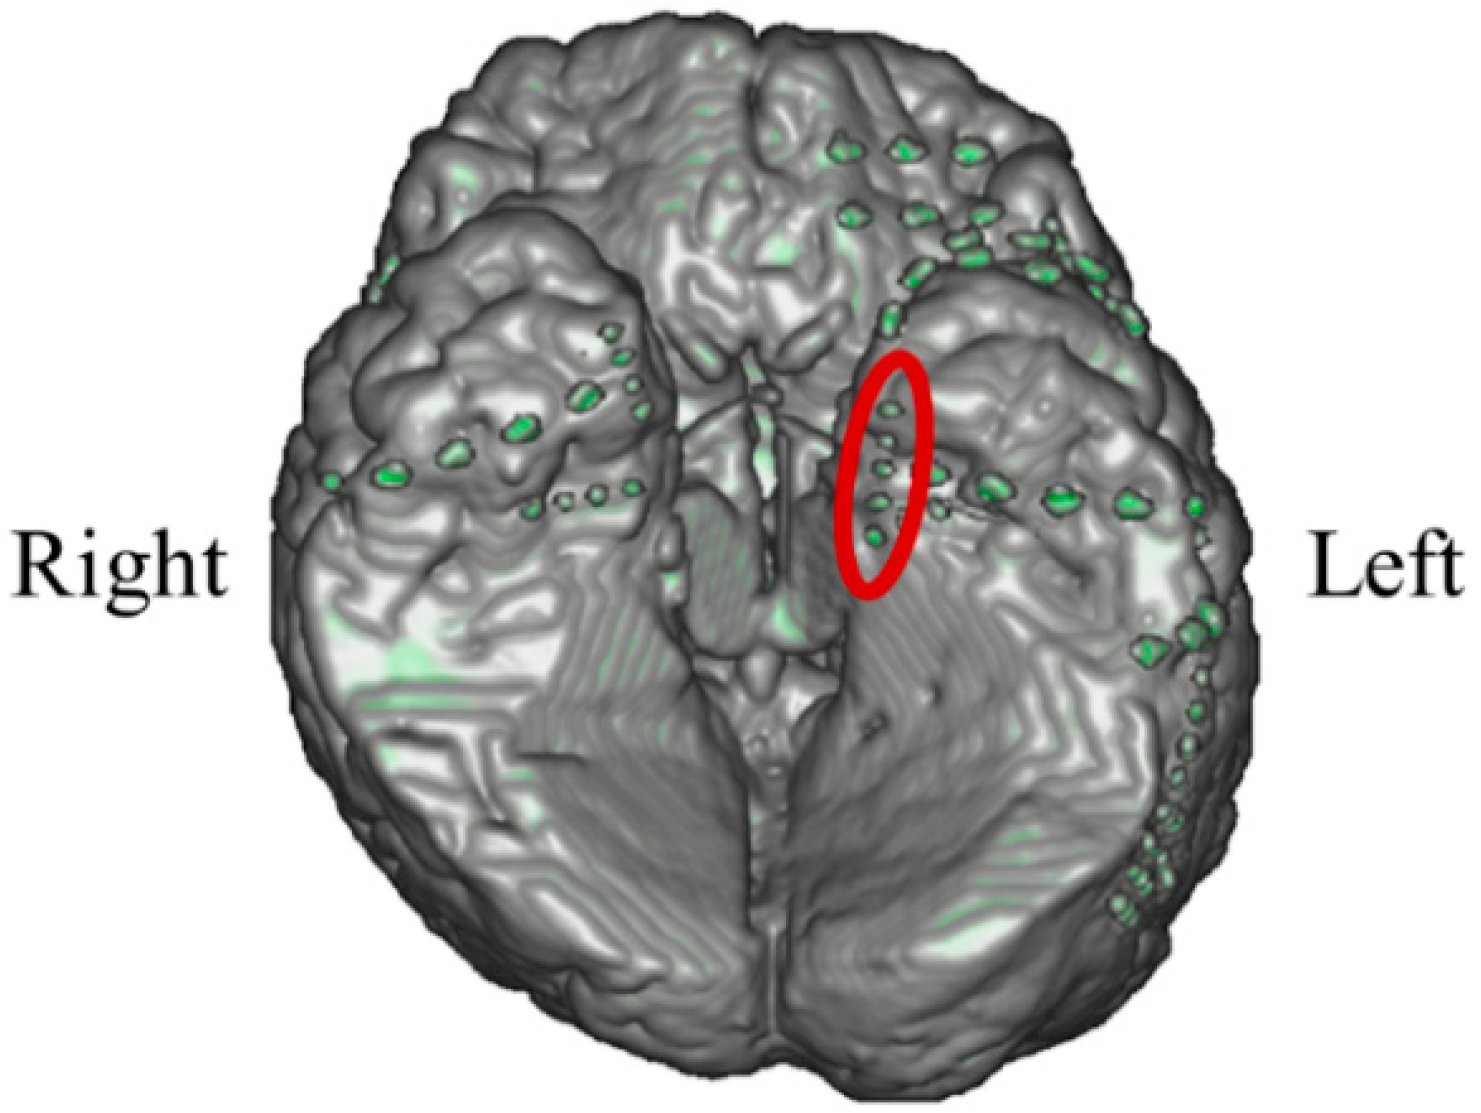

In P02, subdural electrodes (Unique Medical, Tokyo, Japan) were implanted in the left MTL, covering the hippocampus. Four platinum electrodes (1.5 mm in diameter) were longitudinally placed at 5 mm intervals (centre to centre) along the left parahippocampal gyrus, and iEEG was measured and used for NF (Figure 12). A reference electrode placed on the dural side of the right temporal lobe was used for P02.